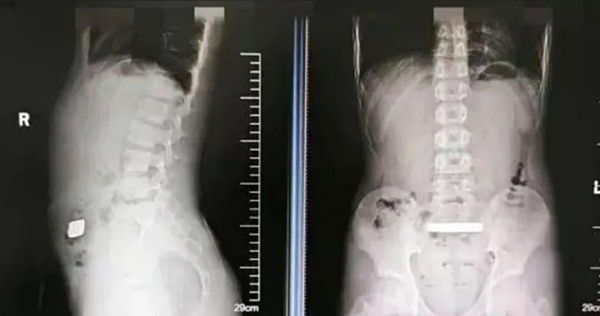

Mới đây, Qian nói với bố mẹ rằng bé thấy bụng mình hơi sưng, dù không đau. Bố mẹ bé lo lắng nên lập tức đưa bé vào Bệnh viện Nhi thuộc ĐH Tô Châu để kiểm tra. Việc chụp X-quang cho thấy có một khối kim loại đặc ở trong ruột của bé.

Nhưng 2 ngày đã qua mà bé Qian vẫn không “cho ra ngoài” thứ gì cả. Bác sĩ thấy khó tin liền chụp X-quang lần nữa thì thấy khối kim loại vẫn ở nguyên vị trí.

| Hình chụp X-quang cho thấy vật thể kim loại nằm trong đường ruột của bé Qian. Ảnh: Douyin. |